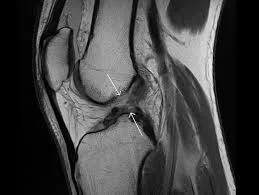

La resonancia magnética de rodilla es una técnica de imagenología que permite detectar condiciones como artritis, tumores, infección, y daños en cartílagos, meniscos, ligamentos o tendones.

A diferencia de las radiografías, una resonancia magnética puede mostrar los huesos, los cartílagos, los ligamentos, los tendones y los músculos de la rodilla en gran detalle. Esto la convierte en una herramienta valiosa para detectar lesiones en los tejidos blandos y evaluar con precisión su estado.

La resonancia magnética de rodilla es un examen de imagenología que ayuda a diagnosticar una variedad de problemas, como: lesiones de ligamentos en los tendones y meniscos, desgarros, roturas y otros daños en la articulación de la rodilla.

Además, su alta tecnología permite detectar condiciones como artritis y problemas óseos como fracturas, tumores y otras anomalías en los huesos de la rodilla en el paciente. En algunos casos, una resonancia magnética de rodilla también se puede usar para guiar inyecciones y planificar una cirugía.